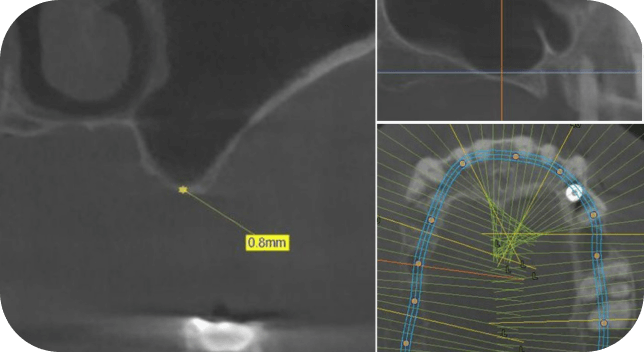

Научитесь работать в особенно сложных ситуациях - выполнять операцию открытый синус-лифт при 1 мм остаточной кости.

1 мм остаточной кости. Что делать?